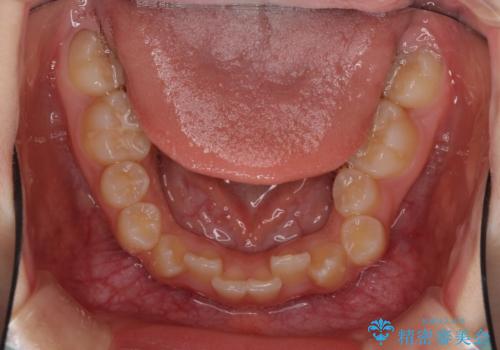

- 急速拡大装置・インビザライン

上顎骨の幅が下顎骨よりも小さいので、拡大装置により骨幅を広げて上下関係を改善し、その後インビザラインにて歯並びを整えることとしました。

上下の骨幅を改善したことで、スムーズに歯列矯正を行うことができました。